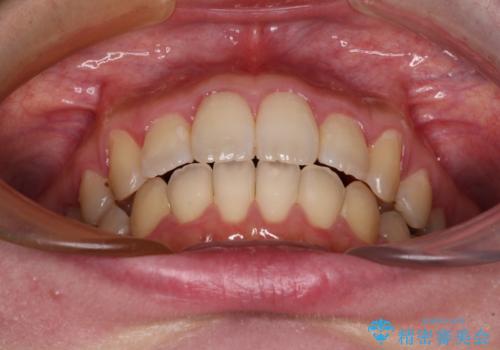

- 捻れた前歯が飛び出しており、口が閉じにくいとのことで来院された患者様です。

出っ歯というわけではないものの、前歯の捻転により口唇が押し出されている状態でした。

親知らずを抜去し、歯列全体を後方に移動させつつ、IPR(歯と歯の間を削る)でスペースを獲得し、インビザラインを用いて叢生を解消しながら前歯の突出を改善することとしました。

インビザラインは、患者様の協力無しには成立しない治療ですが、しっかりと装着時間を遵守してくださり、1年弱で治療を終えることができました。